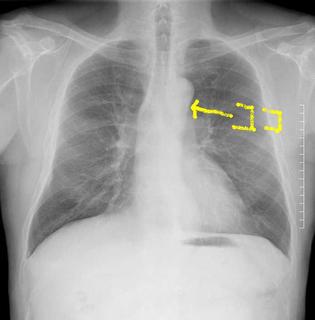

CTで見ると…

3Dだと、こうなります。

気管狭窄ですね。こういう所見もレントゲンで捉えることができるのです。